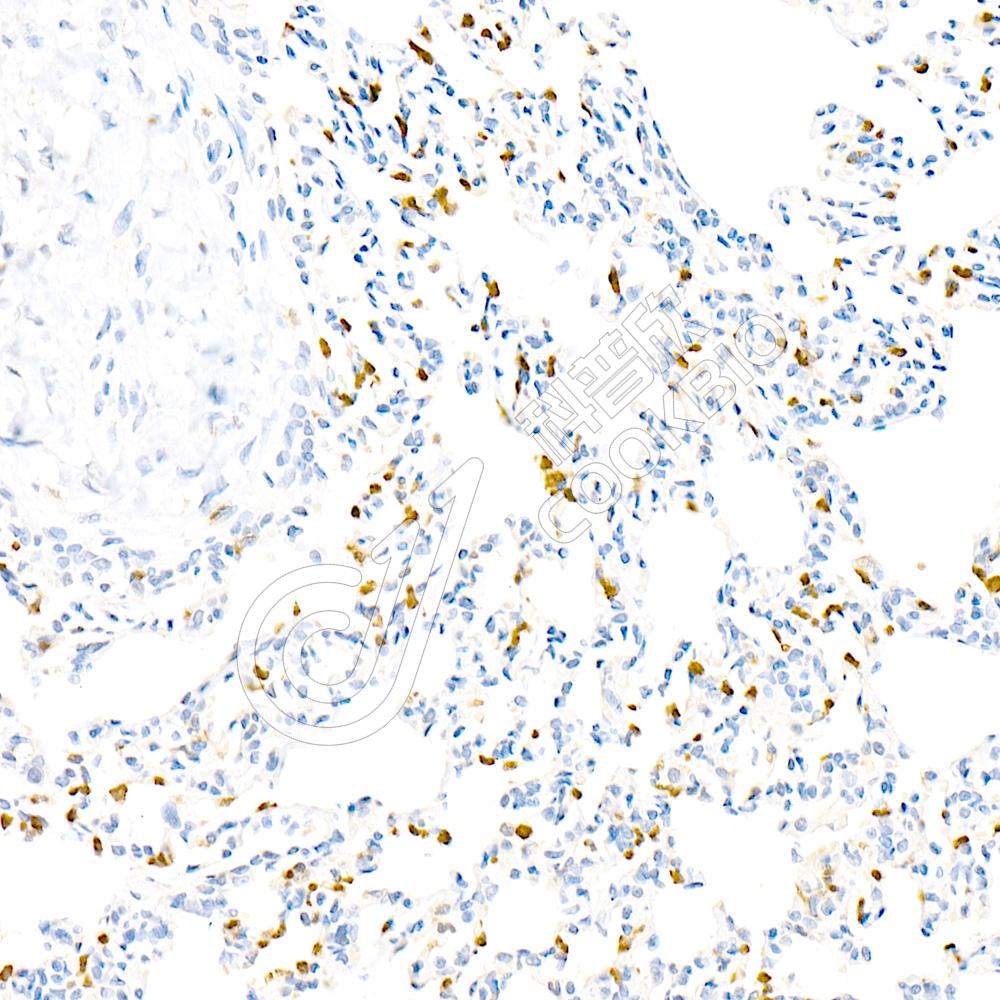

IHC检测IL-10蛋白(货号 K236324).

样品: 大鼠LPS诱导的脓毒症模型肺, 4%多聚甲醛 (货号KSG1101) 固定12-24小时.

抗原修复: 柠檬酸抗原修复液(干粉, pH 6.0) (KSG1201), 98℃, 20分钟.

—抗: 1: 1300稀释, 4℃ 孵育过夜.

二抗: S-vision免疫组化多聚二抗(山羊抗小鼠), 即用型(货号KB3903), 室温孵育20分钟.